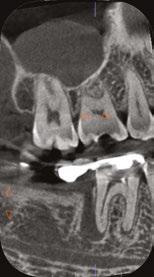

Figure 7: Planned-for access with the scan info on this extremely calcified canine Figures 8 and 9: 8. Deep distal split with PARL. 9. Missed buccal canal; history of previous RCT, post, crown and apico Figure 10: Retreatment consultation. PA from GD Figure 11: Scan images show a previously existing strip perforation

what the literature suggests. And, when I know how many and where the canals are (Figure 13), I can take measurements on the scan and work more efficiently — measuring my working lengths of each canal, appreciating severe curves or calcifications, and knowing where canals can be expected to be located, again, rather than removing unnecessary tooth structure to find if it is there, or not!

As an endodontist, I often treat heavily restored teeth. I am often planning my accesses based on the scan’s information. This saves time and conserves more tooth structure. I’m not looking for canals that may or may not be there, and I’m looking for canals under the targeted/planned access — with the scan, I have an actual map (Figure 7)! CBCT directs me where to go and where to end. It reveals anomalies, which are more common than we think, so I can avoid iatrogenic incidents and provide less invasive treatments. Lower second molars with only two canals occur — often!

I’m also changing my treatment plans based on the data from my CBCT. Sometimes I look at a root canal treated PA and presume I know what I will do: a retreatment or an apico. Another recent, poignant case: a lower incisor with a previous RCT and a previous apico (Figure 9). Usually, once a tooth has had an apico, there may not be much left to offer and most of the time, the default is another apico, especially as there was very little room for an implant on the lower anteriors. I scanned the tooth and saw that a whole canal had been missed — twice! The RCT and the apico had left the buccal canal completely untouched. I changed my treatment plan based on this information!

Cracked teeth are also quite prevalent (Figure 12). Of course, I can suspect them clinically and with transillumination and other tests, I’m fairly confident in my diagnosis. Thankfully, the 3D scan proves it and shows the depth of these cracks and the angular defect. Without a CBCT, sometimes these cases are started unnecessarily.

Lastly, using CBCT also allows me to find issues that should be evaluated by another specialist. For example, when I capture incidental sinusitis, I can inform my patient to see an MD or ENT and can provide the 3D images to share with their physicians; or, to involve another dental specialist. (Figures 2, 4, 6, and 11 show incidental sinus findings.)